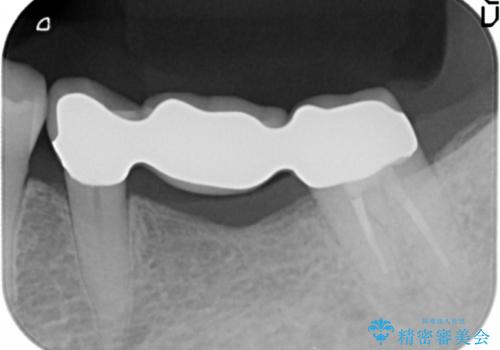

精査したところ、ブリッジの支台歯となっている左下の奥歯(左下7)は大きなう蝕により神経が死んでいました。

根管治療後、メタルボンドブリッジによる補綴治療を行いました。

クラウンの種類:メタルボンドクラウン エコノミー